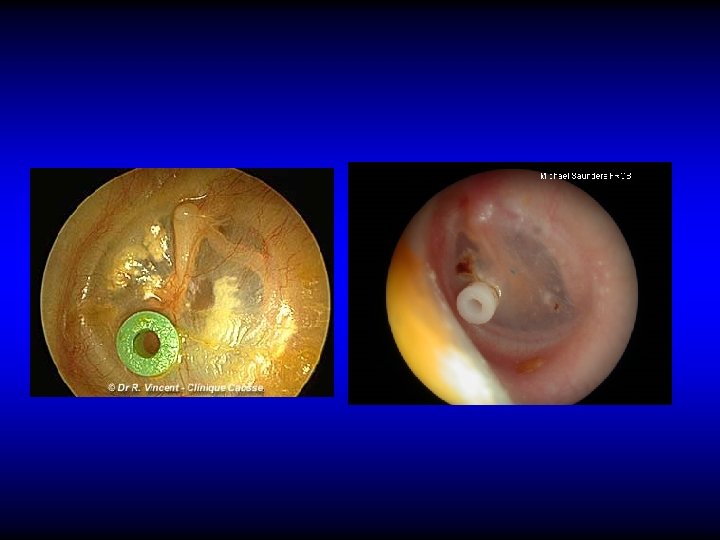

Treatment • Treatment of the cause if feasible • Observation • ? Medical treatment – Antibiotics – Decongestants, ? Auto-inflation • Surgical – Ventilation tubes (grommets) insertion

Ventilation tubes insertion

Other indication for VT insertion • Repeated attacks of AOM

Complications of Ventilation Tubes • Infection

Complications of Ventilation Tubes • Infection • Blockage

Complications of Ventilation Tubes • Infection • Blockage • Early extrusion

Complications of Ventilation Tubes • Infection • Blockage • Early extrusion • Tympanosclerosis

Complications of Ventilation Tubes • Infection • Blockage • Early extrusion • Tympanosclerosis • Persistent perforation